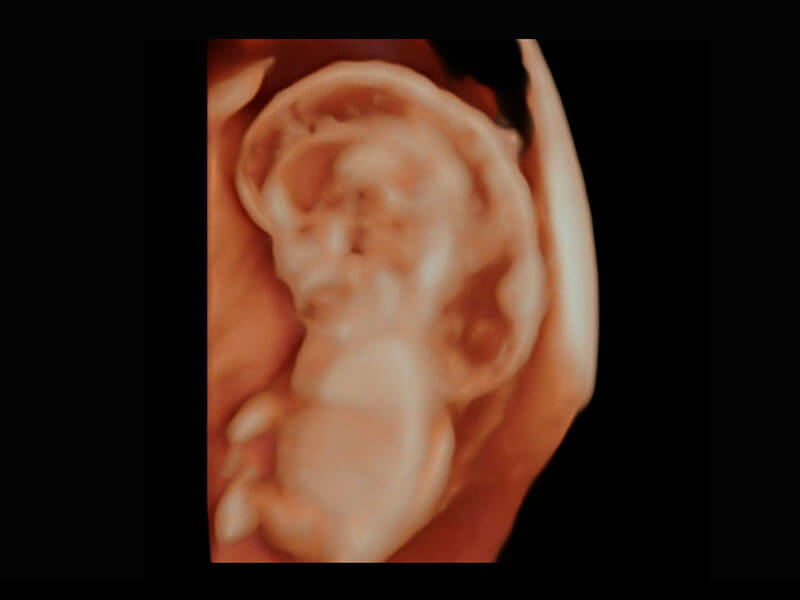

P60搭载一系列胎儿心脏成像技术,实现精细的胎儿心脏评估。

胎心容积成像